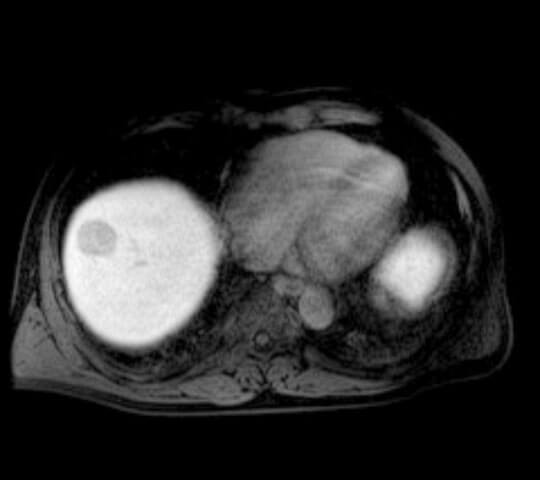

EOB(肝臓腫瘍精密検査)